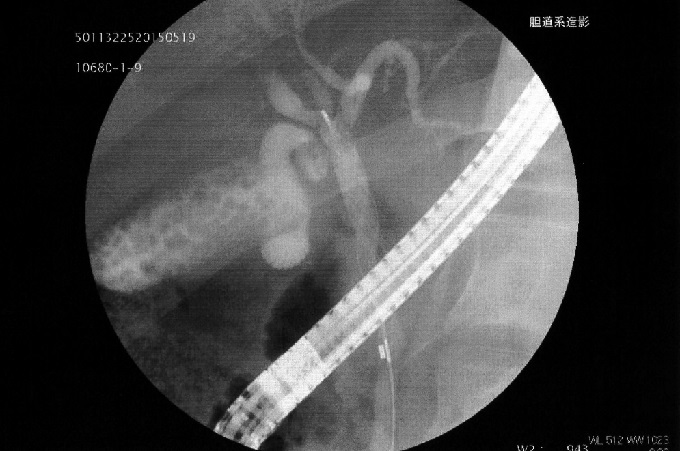

胃カメラを使って胆のう周りを撮影した上に、石が詰まらなくなるようチューブを取り付けるという手術を、当日いきなり受けた。さらに回復を待って、5日目には総胆管に詰まった石を、胃カメラに取り付けたバルーンで十二指腸に落っことす、という手術も。いずれも全身麻酔で行われたが、術後はノドや患部がズキズキと傷んだものだった。